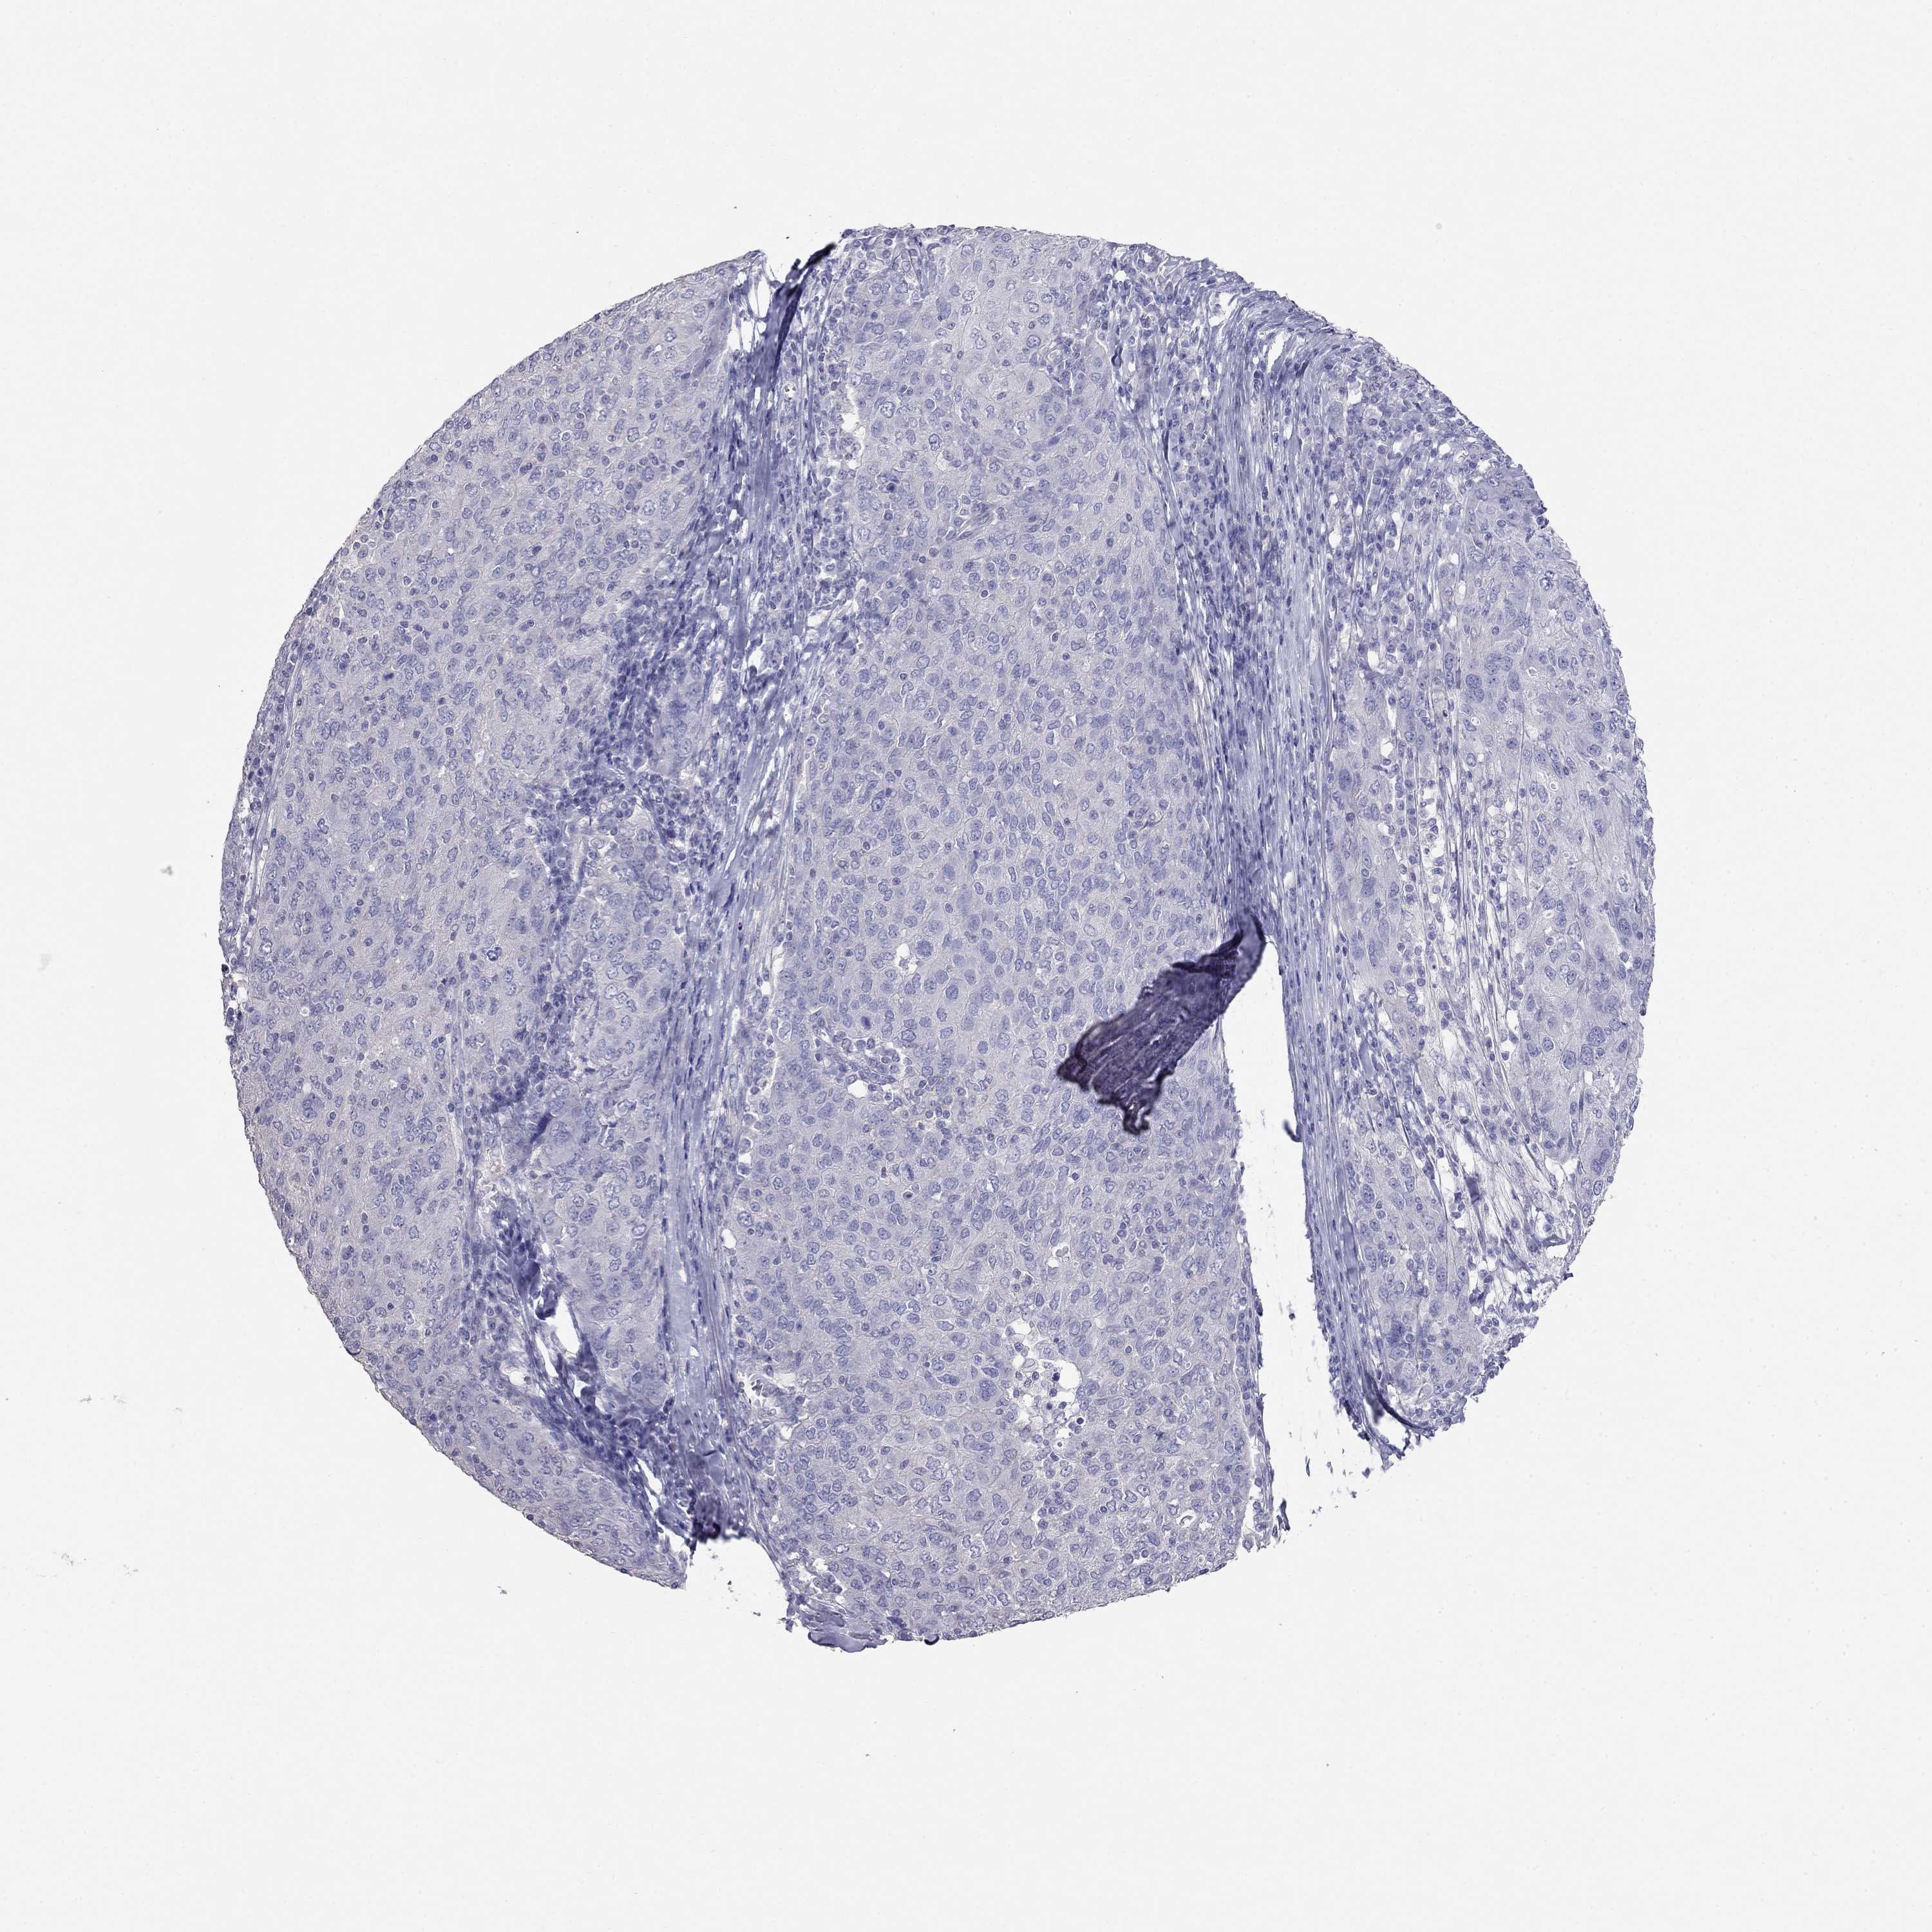

OVARIAN CANCER - Protein expressioni

A mouse-over function shows sample information and annotation data. Click on an image to view it in a full screen mode. Samples can be filtered based on level of antibody staining by selecting one or several of the following categories: high, medium, low and not detected. The assay and annotation is described here.

Note that samples used for immunohistochemistry by the Human Protein Atlas do not correspond to samples in the TCGA dataset.

Antibody stainingi

Antibody staining in the annotated cell types in the current human tissue is reported as not detected, low, medium, or high, based on conventional immunohistochemistry profiling in selected tissues. This score is based on the combination of the staining intensity and fraction of stained cells.

Each image is clickable and will lead to virtual microscopy that enables deeper exploration of all samples and also displays staining intensity scores, fraction scores and subcellular localization as well as patient and tissue information for each sample.

Antibody HPA077218

Cystadenocarcinoma, serous, NOS

Cystadenocarcinoma, mucinous, NOS

Carcinoma, endometroid